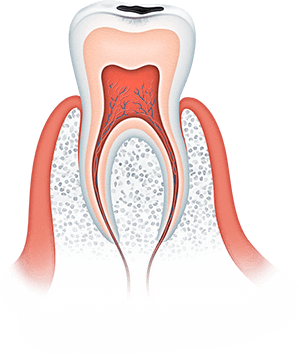

Большинство стоматологических заболеваний необратимые

Важно помнить, что большинство стоматологических заболеваний необратимые, кариозная полость сама по себе не зарастает, костная ткань при пародонтите не восстанавливается, а утраченные зубы не вырастают заново. Болезни полости рта при отсутствии своевременного лечения прогрессируют: кариес превращается в пульпит, пульпит в периодонтит, последний очень часто приводит к потере зуба.